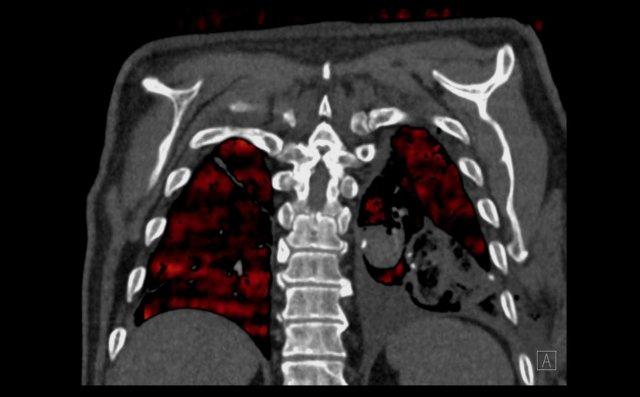

Hình ảnh

Cuộn qua các hình ảnh.

Theo dõi các phế quản của thùy dưới phổi trái cho thấy nhánh phân thùy đầu tiên của thùy dưới phổi trái còn thông; đó là phế quản phân thùy đỉnh.

Các ghim phẫu thuật nằm tại vị trí của các phân thùy đáy sau và đáy bên (LB9/10), vốn thường được cắt bỏ cùng nhau.

Do đó, phân thùy phổi có hình ảnh kính mờ và đông đặc phải là phân thùy đáy trước của thùy dưới phổi trái (LB8).

Động mạch phổi đến phân thùy này cũng không ngấm thuốc cản quang, và bản đồ tưới máu iốt nhấn mạnh thêm tình trạng nhồi máu.

Bệnh nhân đã được phẫu thuật lại và tiến hành cắt bỏ phân thùy bị nhồi máu, với xác nhận qua giải phẫu bệnh.

Tiếp tục với bản đồ tưới máu…

Trên bản đồ tưới máu iốt, có sự tưới máu ở thùy trên phổi trái và phân thùy đỉnh của thùy dưới phổi trái, nhưng không có sự tưới máu ở phân thùy đáy trước của thùy dưới phổi trái.